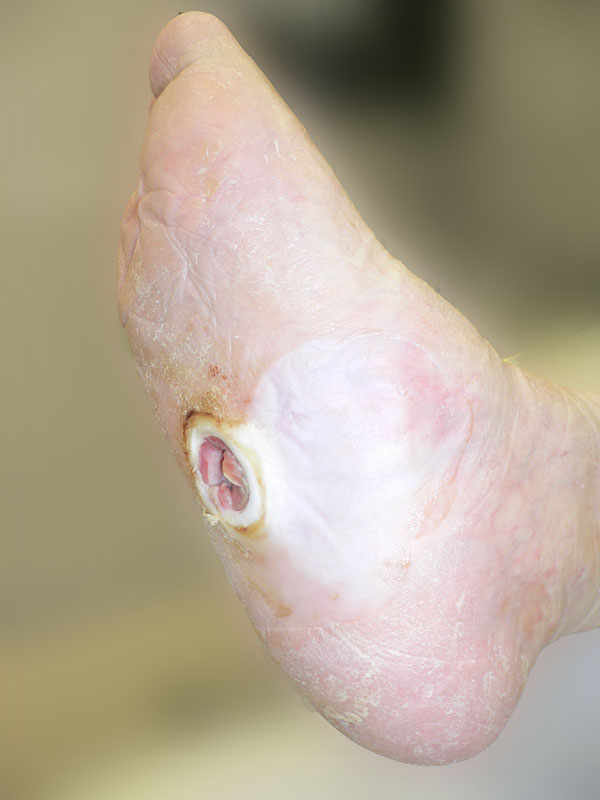

Am liegenden Patienten wird insbesondere die Fußsohle inspiziert. Neben der Beurteilung von Hautfeuchtigkeit und -temperatur ist die Oberflächenbeschaffenheit gerade beim DFS genau zu prüfen und nach evtl. vorhandenen Fehlbeschwielungen, Rhagaden, subkeratotischen Einblutungen und Hämatomen zu fahnden. Bei manifestem Ulcus erfolgt eine exakte Klassifikation (Wagner-Armstrong-Klassifikation), die Beschreibung der Lokalisation und Ausdehnung sowie eine Fotodokumentation der Läsion.

Unter normalen Bedingungen findet sich eine gleichförmige Beschwielung unter dem gesamten Vorfuß, der lateralen Hälfte des Mittelfußes und unter der gesamten Ferse. Hyperkeratosen sind an unphysiologischer Lokalisation ein zuverlässiger Indikator für eine pathologische Fehlbelastung. Neben einer Beurteilung von Hautkoloritveränderungen (DD Infektion, pAVK, Osteoarthropathie, venöse Stauung, Ekzeme usw.) sind vor allem die Zehenzwischenräume auf Zeichen einer Dermatomykose zu prüfen. Der Bereich der Zehennägel ist bedingt durch die hohe Indzidenz von Onchomykosen beim Diabetiker, ein Einwachsen im Nagelrandbereich (Unguis incarnatus) und Verletzung benachbarter Zehen durch unzureichende oder falsche Pflege der oft hypertrophen Nägel ein häufiger Ausgangspunkt von Infektionen und Ulzerationen (Abb. 4).